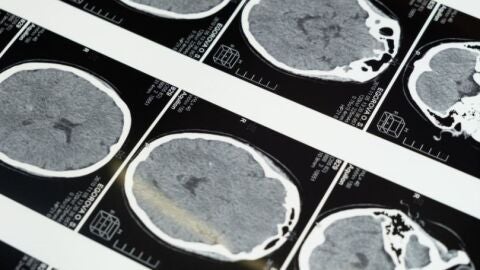

Hoy se conmemora el Día del Daño Cerebral Adquirido (DCA), con la finalidad de sensibilizar a la población y poner el foco en las necesidades de atención, de rehabilitación y reinserción social de las personas con daño cerebral adquirido o sobrevenido. una discapacidad que afecta a cerca de medio millón de personas en nuestro país, 20.000 de ellas en la Comunidad Autónoma de Castilla la Mancha.